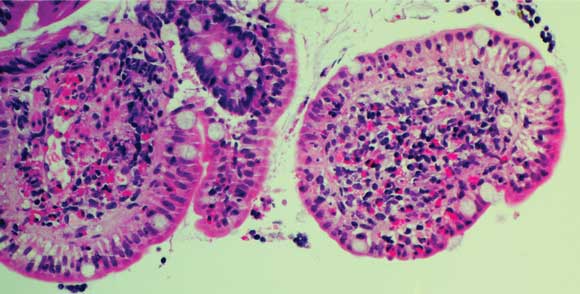

Colonoscopy revealed mild terminal ileitis. Biopsies of the affected area showed an eosinophilic infiltrate in the lamina propria and submucosa, but intact surface epithelium. Occasional adult worms measuring about 70 μm wide at the midbody were seen on the luminal surface (Box 1A and B), and were initially identified as Enterobius vermicularis. He was treated with two 100 mg doses of mebendazole 1 week apart. However, he re-presented 3 weeks later with no improvement in his symptoms and a persistent eosinophilia (1.4 × 109/L).

1 Samples from Patient 1

A: Biopsy of terminal ileum showing eosinophilic infiltrate in the lamina propria and submucosa, with a parasite on the luminal surface. B: Enlargement of parasite. C: Iodine wet mount of faecal specimen showing a Trichostrongylus egg. |